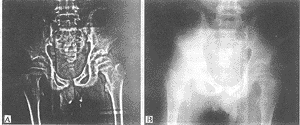

图1 使用CR边缘增强及对比度反转

A. 示左侧股骨头骨骺密度不均匀,关节间隙相对增宽 B. X线片未见异常

图2 A.改变CR对比度示右侧股骨头骨质疏松; B.X线片未见异常

常规X线平片是诊断股骨头坏死的首选检查,由于它不能显示出Ficat 0~Ⅰ期股骨头坏死,多年来许多学者为解决早期诊断问题进行了大量的研究和探讨[4-6]。骨扫描虽可检出股骨头部吸收增加或减少,但不能鉴别股骨头坏死与其它疾病,例如炎症,感染或肿瘤。骨内压测定或静脉造影系侵入性检查,一般不能作为髋痛的初始检查方法。MRI对早期诊断股骨头缺血性坏死敏感性高达100%。由于价格昂贵,在我国广泛普及受到了限制,本组Ⅰ期2髋经CR检出(表1)。1髋使用CR显像边缘增强及对比度反转,清楚显示出股骨头骨骺密度不均匀,关节间隙相对增宽(图1)。另1髋通过改变CR的对比度,清楚地显示了股骨头骨质疏松(图2)。Ⅱa期1髋通过改变CR的对比度,清楚显示股骨头骨质稀疏及头下小囊变。以上3例在常规X线平片上均未诊断出。其它10髋Ficat法分期Ⅱb~Ⅳ期,CR与常规X线平片相比检出率无差异。以上结果表明CR检查对股骨头缺血性坏死的早期诊断优于常规X线平片。由于本组样本量较小,这项研究未能对CR 早期诊断股骨头坏死的敏感性和特异性进行评价,上述结论在临床应用推广之前,有必要进行较大样本量的临床研究证实。